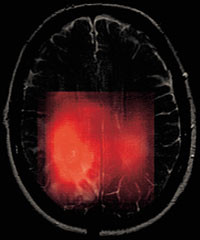

In vivo-MRS-observasjoner av endret metabolisme kan være nyttig f.eks. for å bestemme hvor overgangen går mellom kreftvev og normalt vev, og for å skille mellom arrvev etter operasjon og strålebehandling fra tilvekst av nytt kreftvev (8). Ett av de viktigste områdene for bruk av MRS vil være oppfølging av pasienter der det er spørsmål om tumorresidiv. Klassifisering av svulstene er til en viss grad mulig ved hjelp av in vivo-MR-spektroskopi i kombinasjon med avansert dataanalyse (9, 10). Et eksempel på et CSI-bilde av kolin er vist i figur 4. Det forhøyede kolinnivået stemmer overens med tumorområdet i MR-bildet.